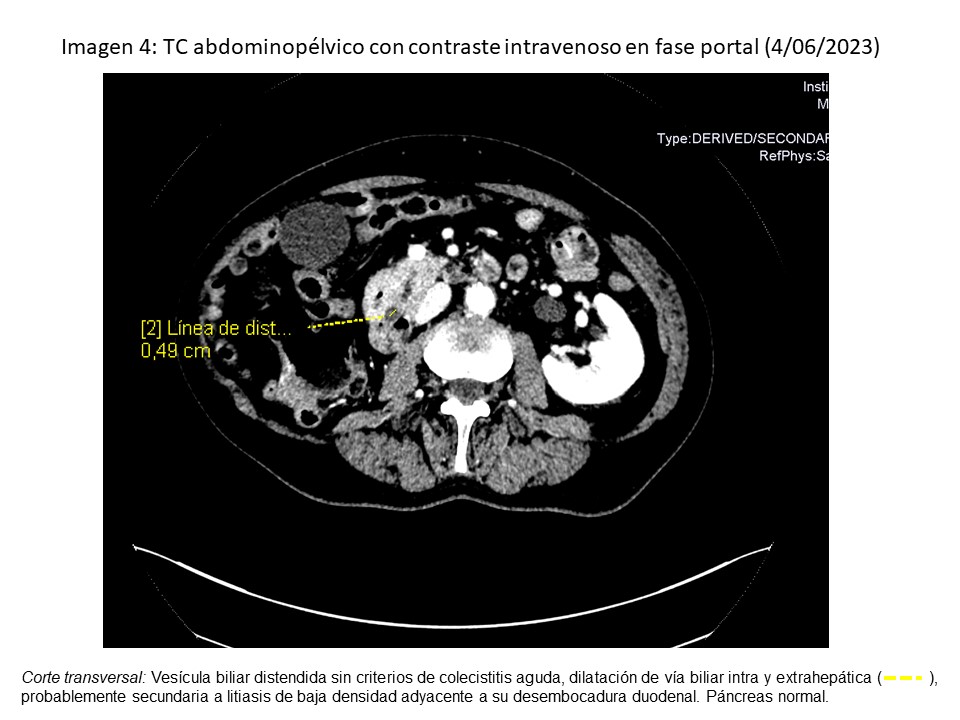

• Analítica (04/06): BT 5.59 (directa 5.31, indirecta 0.28), GPT 335, Amilasa 539, PCR 7.85, leucocitos 11.240 (neutrófilos 10.630).

• TC abdominopélvico (4/06/2023): dilatación de vía biliar intra y extrahepática, por litiasis.